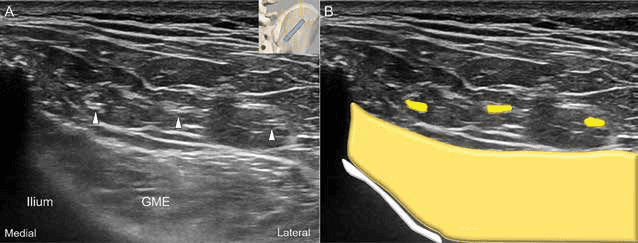

초음파 영상에서 상둔신경 분지들의 단축 영상을 통해 신경의 횡단면 구조를 명확히 관찰할 수 있었습니다. 수압박리술 - 그림 4. 초음파 영상(A)과 상둔신경 분지들의 단축 영상에 대한 개략도(B)입니다. Figure 4. 그림 4. 초음파 영상(A)과 상둔신경 분지들의 단축 영상에 대한 개략도(B)입니다.

상둔신경 분지들의 다양한 단축 영상 패턴을 초음파로 구분하여 진단 정확도를 높였습니다. 수압박리술 - 그림 5. 상둔신경 분지들의 단축 영상에 대한 초음파 영상(A)과 개략도(B)입니다. Figure 5. 그림 5. 상둔신경 분지들의 단축 영상에 대한 초음파 영상(A)과 개략도(B)입니다.